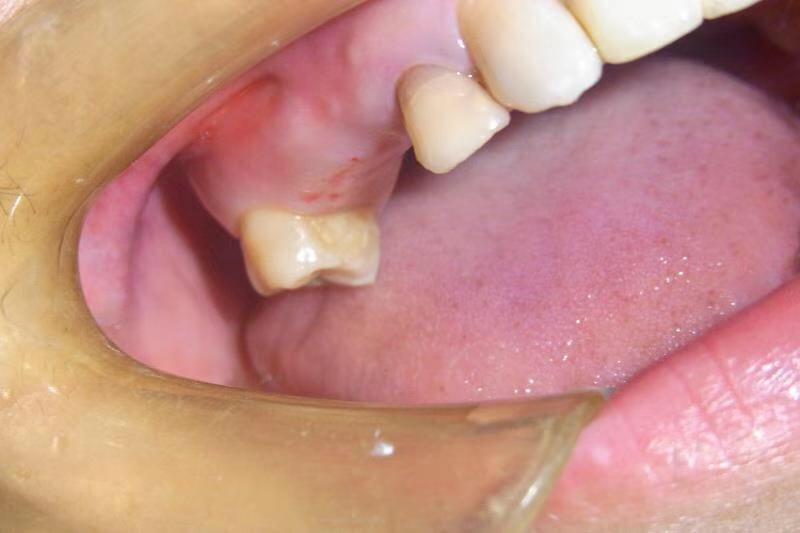

患者女,右上4号牙根管治疗后桩核冠修复,因进食硬物导致桩核冠脱落,未及时处理,导致残根无法修复,从CT上看,牙槽骨高度尚可,所以选择了即拔即种的治疗方案,且术中植骨盖膜、上愈合基台,为患者节省了就诊次数,提前了戴牙时间。